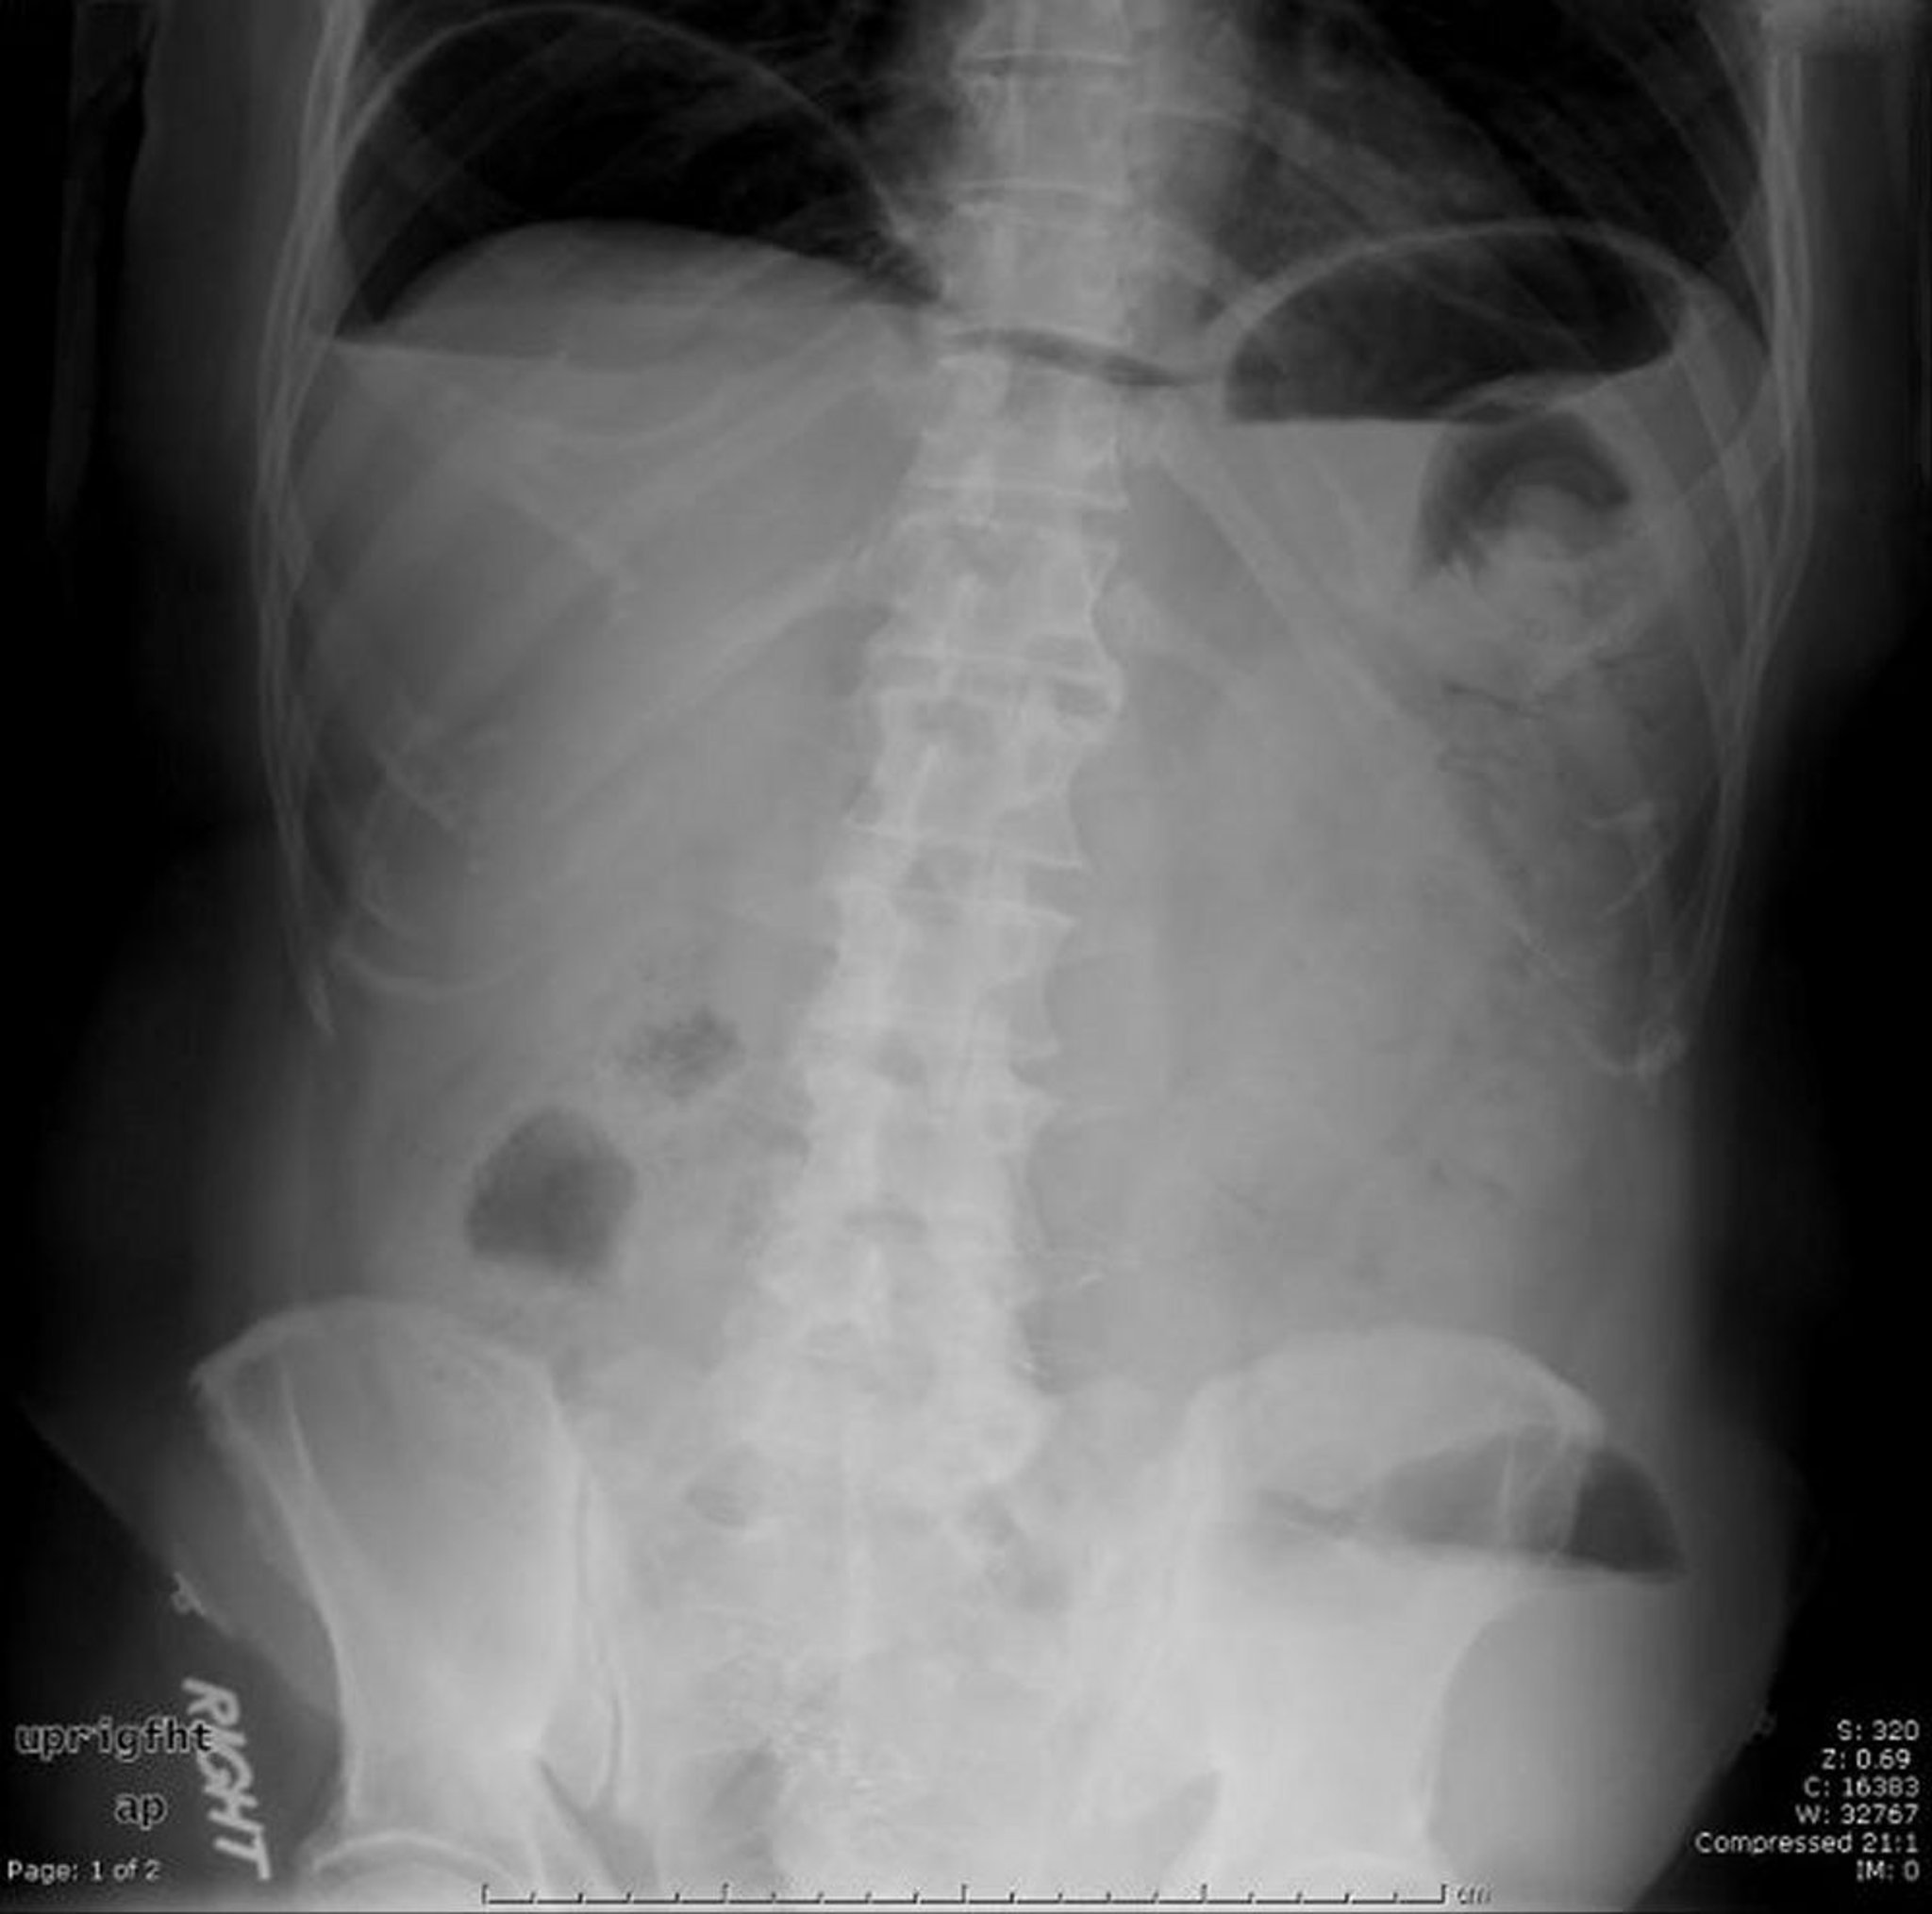

Cette radiographie abdominale montre de l'air libre causé par une perforation.

Image provided by Parswa Ansari, MD.